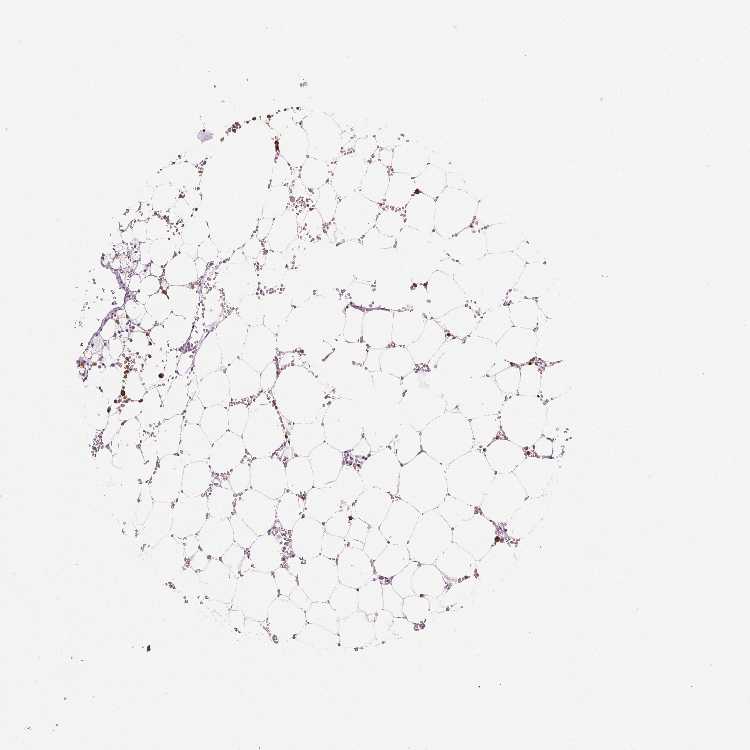

BONE MARROW - Antibody stainingi

Antibody staining in the annotated cell types in the current human tissue is reported as not detected, low, medium, or high, based on conventional immunohistochemistry profiling in selected tissues. This score is based on the combination of the staining intensity and fraction of stained cells.

Each image is clickable and will lead to virtual microscopy that enables deeper exploration of all samples and also displays staining intensity scores, fraction scores and subcellular localization as well as patient and tissue information for each sample.

Antibody HPA021147Antibody HPA061464Antibody CAB000059Antibody CAB080352Antibody CAB080353Antibody CAB080354

Hematopoietic cells LowHighMediumHighHighHigh